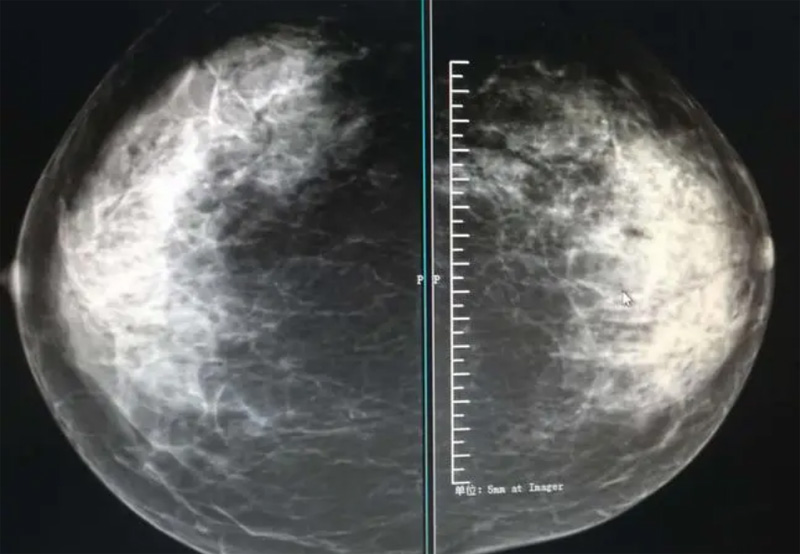

攝影診斷規(guī)范乳腺DR有頭尾位及內(nèi)外側(cè)斜位診斷概念和診斷術(shù)語

乳腺DR的檢查中為了讓乳腺相關(guān)疾病的篩查需要更高質(zhì)量的檢查圖像。檢查前期的準(zhǔn)備工作非常重要。醫(yī)生跟病患的有效溝通。要跟檢查者說明檢查過程,特別是體位跟擠壓乳房帶來的不適應(yīng)。放松心情,檢查過程中得到充分的合作。正確的擺正位置乳腺DR可以拍攝到更優(yōu)質(zhì)清洗高質(zhì)量的X線圖像。乳腺DR檢查需要再月經(jīng)后檢查,但是對(duì)病癥明顯的就不受這個(gè)限制。

乳腺DR攝影體位有頭尾位及內(nèi)外側(cè)斜位,

乳房在片子的中央,乳頭切線位,可見小部分胸大肌,內(nèi)側(cè)乳腺組織應(yīng)全部包括在片中,外側(cè)乳腺組織盡可能包括在片中。一張好的MLO位圖像顯示如下:乳房被推向前上,乳腺實(shí)質(zhì)充分展開,胸大肌可見,較松弛,下緣達(dá)到乳頭水平,乳頭在切線位,部分腹壁包括在片中,但與下部乳腺分開,絕大部分乳腺實(shí)質(zhì)顯示在片中。乳腺組織外緣可見乳頭的輪廓;乳腺后方的脂肪組織被很好地顯示出來,乳房無皺褶。對(duì)于CC位及MLO位顯示不良或未包全的乳腺實(shí)質(zhì),可以根據(jù)病灶位置的不同選擇以下體位:外內(nèi)側(cè)位(LM)、內(nèi)外側(cè)位(ML)、內(nèi)側(cè)頭尾軸位(MCC)、外側(cè)頭尾軸位(LCC),尾葉位(CLEO)及乳溝位。在臨床實(shí)踐中,對(duì)于常規(guī)體位上發(fā)現(xiàn)的異常改變,可以進(jìn)一步采取一些特殊的攝影技術(shù),包括局部加壓攝影、放大攝影或局部加壓放大攝影技術(shù)。

2、規(guī)范觀圖程序:屏幕軟閱讀或在專用日光觀片燈下膠片閱讀,后者應(yīng)同時(shí)準(zhǔn)備白熾強(qiáng)光燈及觀片放大鏡。注意雙側(cè)乳腺配對(duì)觀察,推薦雙眼橫向掃描,進(jìn)行雙乳相同部位圖像比較分析。

3、乳腺實(shí)質(zhì)背景的確定:觀察乳腺實(shí)質(zhì)與脂肪的構(gòu)成比例,了解乳腺實(shí)質(zhì)類型,以判斷對(duì)某些乳腺攝影征象敏感性的影響,有利于確定乳腺攝影對(duì)疾病的診斷價(jià)值。